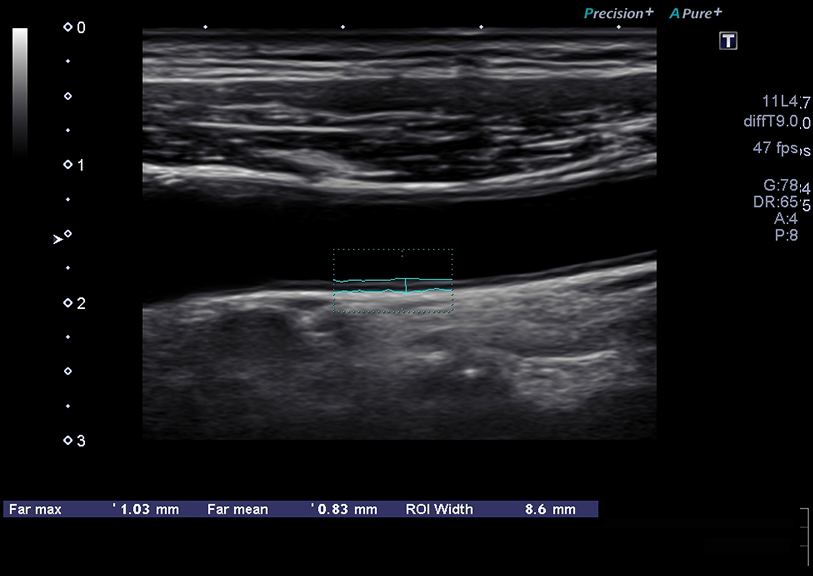

Fast, semi-automated measurement.

Auto-IMT

Auto-IMT (Intima-Media Thickness) semi-automatically measures the intima-media thickness of the arterial walls on user selected ultrasound images of carotid arteries.